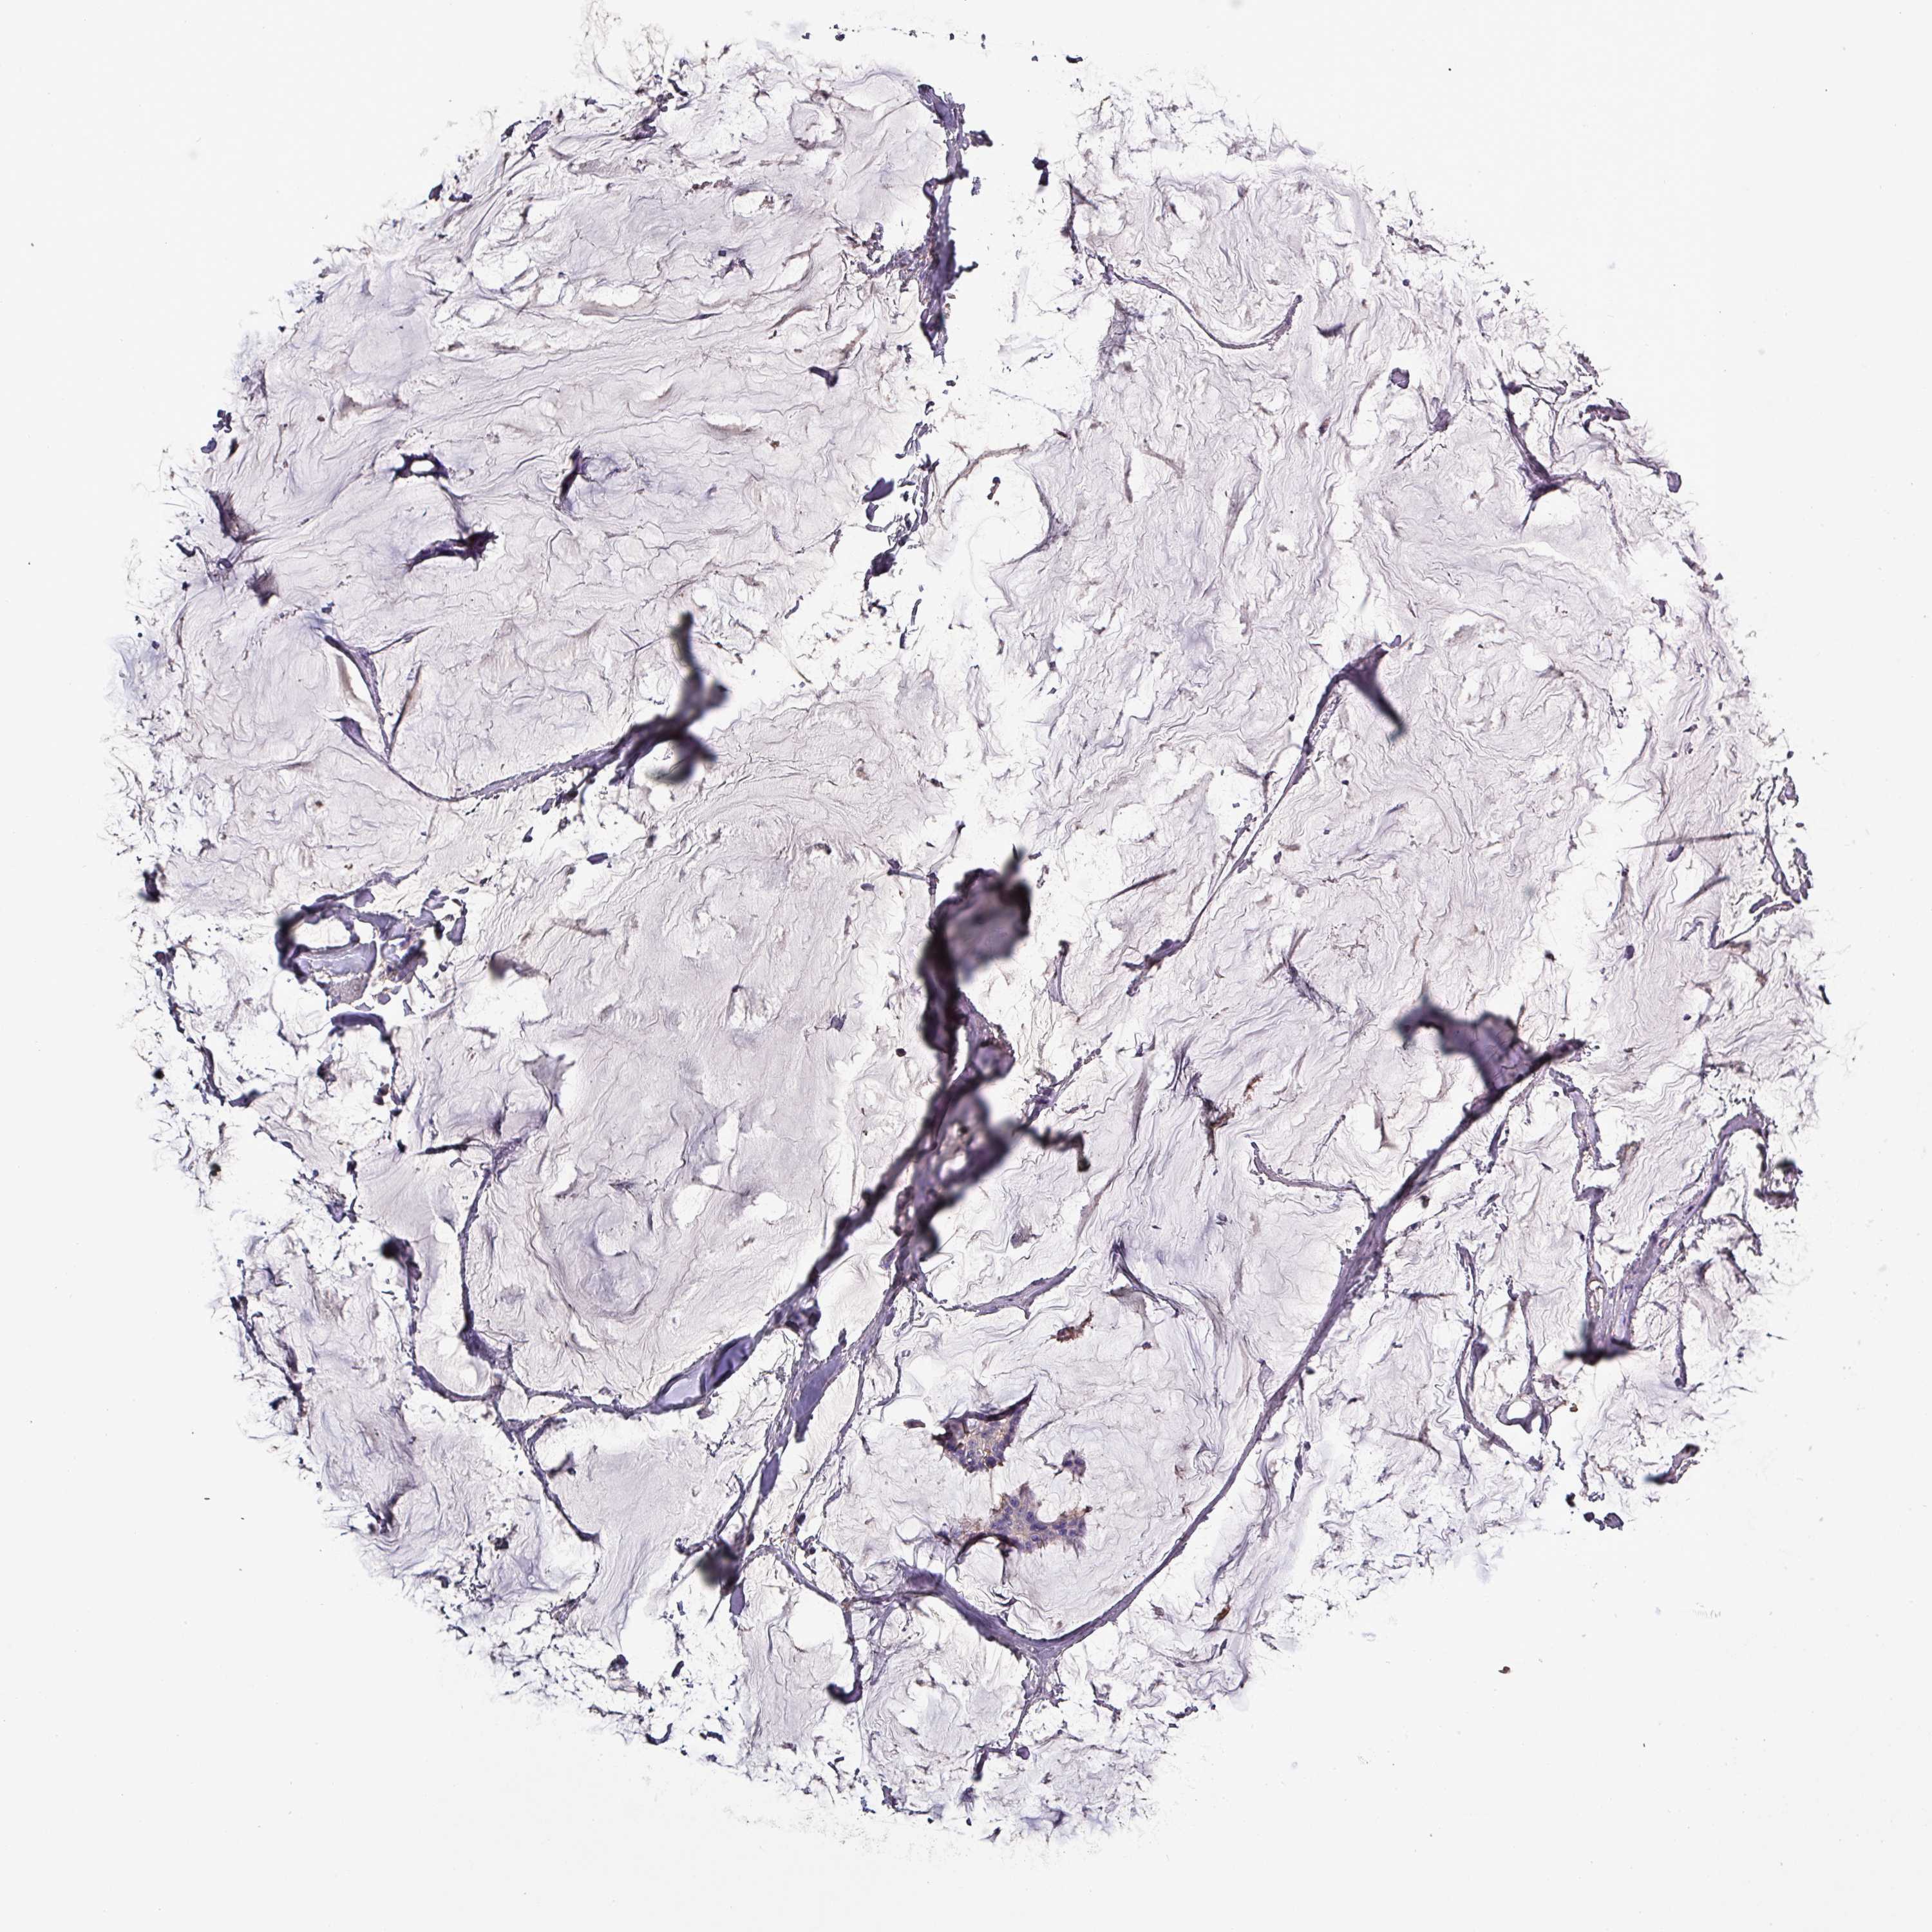

Breast cancer

Human cancer